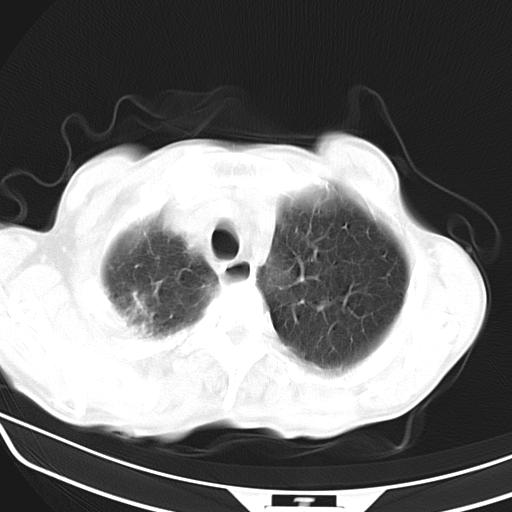

男,70,发烧咳嗽咳痰10余天,查痰结核菌阴性。否认以前有肺病史。治疗10天后症状减轻。 img]/upload/forum/2009/12/302117469692.jpg[/img]

双肺多发斑片状条索样及网格状改变,右上肺可见大个空洞,首先考虑tb慢性炎症并空洞形成。

双肺多发斑片状条索样及网格状改变,右上肺可见大个空洞,首先考虑tb慢性炎症并空洞形成。特发行纤维化。肺癌待排。

影像所见:右上肺见一巨大厚壁空洞,内壁欠光整,右上肺广泛斑片状、大片状模糊阴影。

影像所见:右上肺见一巨大厚壁空洞,并见分隔,内壁欠光整,右上肺广泛斑片状、大片状磨玻璃阴影。